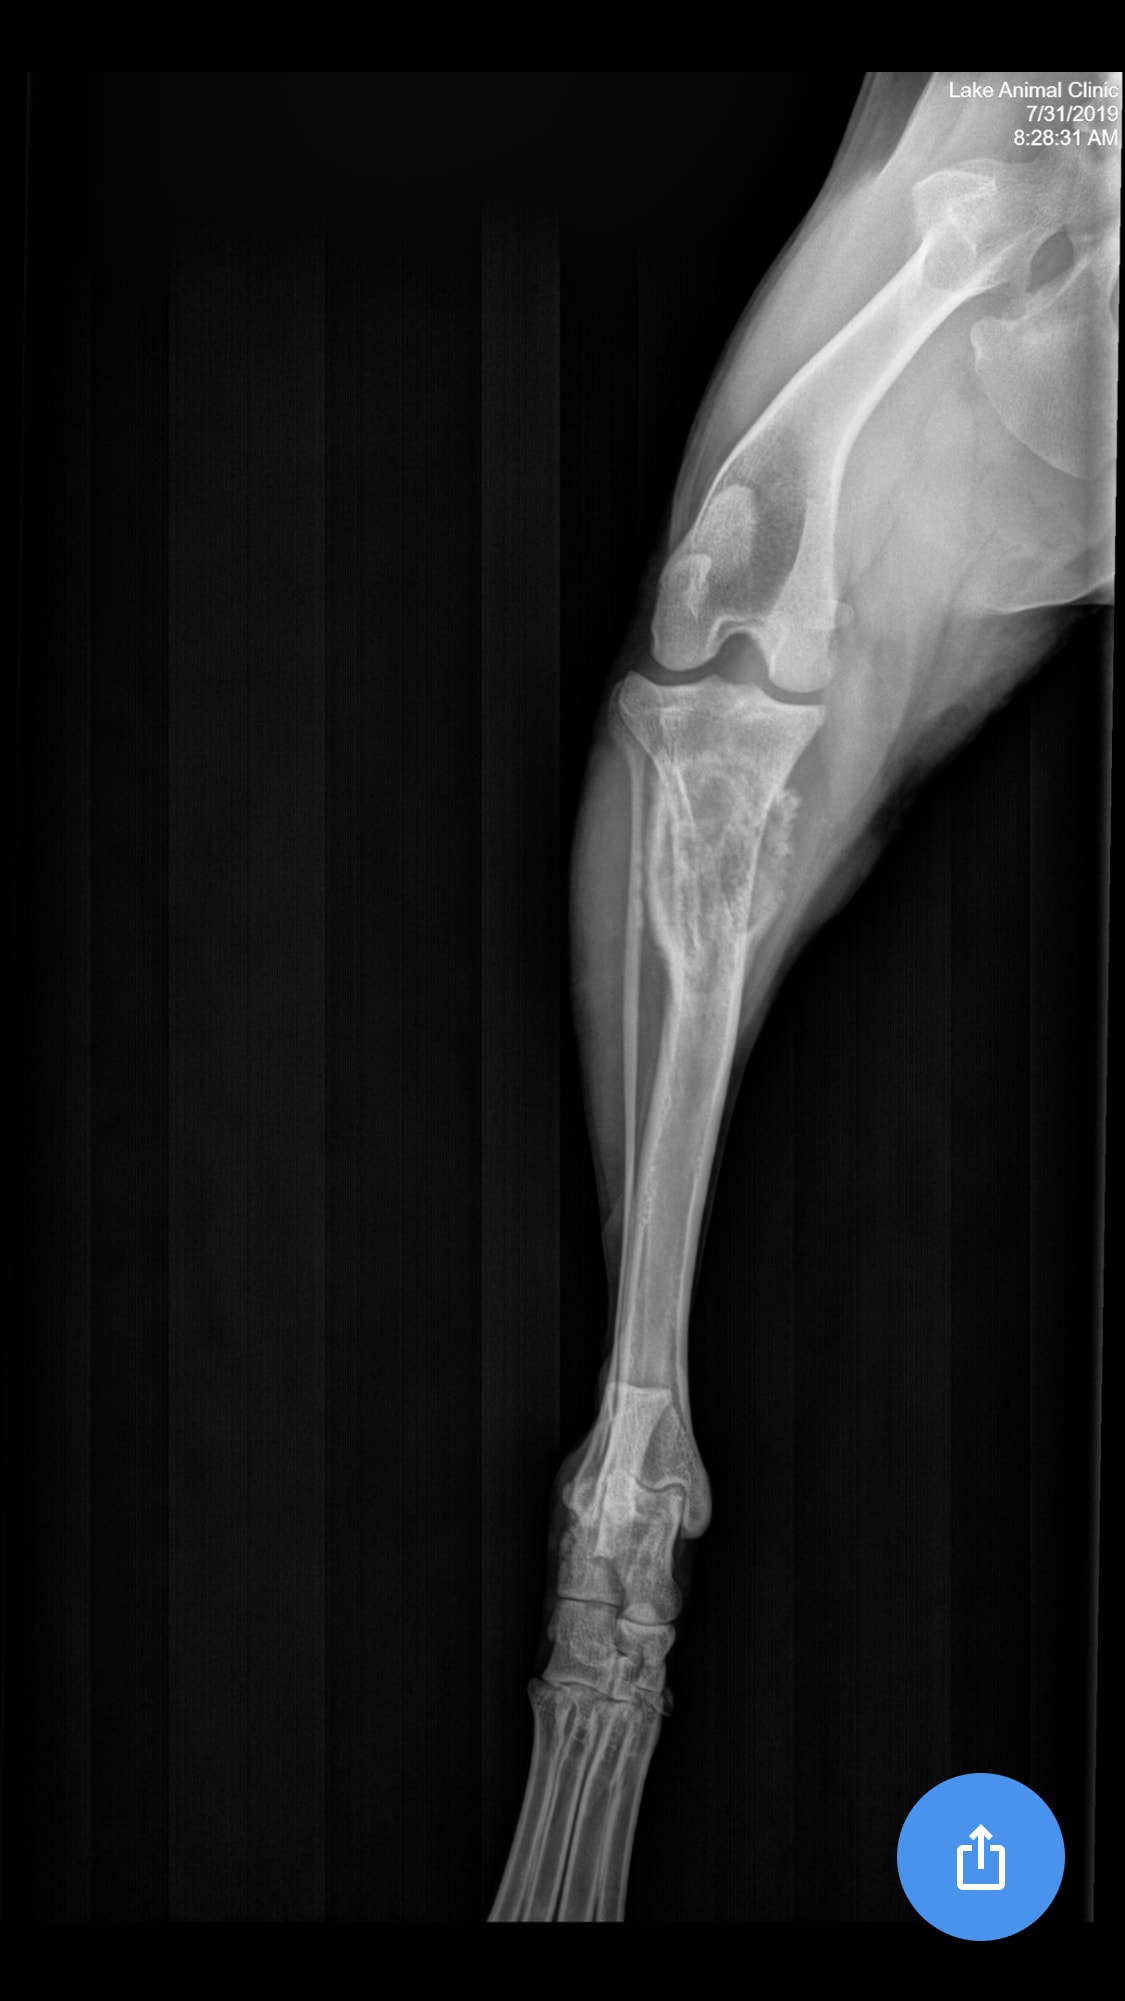

Pet's info: Dog | Goldendoodle | Male | 4 years and 4 months old | 48 lbs

Is this osteosarcoma? My vet said it was but could it be anything else?

Thanks for using Petco Pet Education Center, formerly Petcoach! I would agree that the primary differential based on this radiographs would be a primary bone tumor being osteosarcoma the most common one. However, other things such as a fungal infection depending on the state you live in, is also possible. The next step would be sampling of this lesion via fine needle aspiration or biopsy to confirm the diagnosis. If confirmed, therapy can be discussed at that time. I'm hoping for the best!